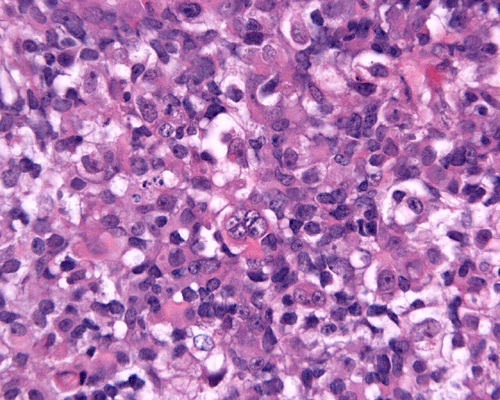

Pathology

Rhabdoid cells are medium sized to large, oval to round cells. In the most classic example, the rhabdoid cell contains an eosinophilic, hyaline-like cytoplasmic globule resembling an inclusion body and occupies a large portion of the cytoplasm. This hyaline globule displays the nucleus to an eccentric location. The less classic examples contain a substantial amount of eosinophilic, often hyaline-like cytoplasm and eccentrically located nuclei. Although the morphologic features are suggestive of a rhabdomyosarcoma, cytoplasmic striations typical for rhabdomyoblastic differentiation should not be present. Marked pleomorphism is seen in most cases and nucleoli are usually prominent. Multinucleated giant cells are common. Mitotic figures and atypical mitosis are common. The degree of necrosis is variable but may not be extensive.

Only about 13% of AT/RTs are composed exclusively of rhabdoid cells. Non-rhabdoid components are seen in the rest. About two third to three quarter of AT/RTs are associated with medulloblastoma or primitive neuroectodermal tumor (PNET) like components. Neoplastic epithelial components may occur as adenocarcinoma-like components, squamous cell with keratinization, or just simply epithelial cells arranged in nests. Neoplastic mesenchymal components can also be seen. The amount of rhabdoid cells can vary greatly from uncommon to substantial. AT/RT with substantial medulloblastoma/PNET like component may be mistaken as medulloblastoma or PNET [Burger PC et al., 1996]. Under the electron microscopy, rhabdoid cells contain bundles of tightly packed intermediate filaments arranged in whorls.

Immunohistochemistry, the defining diagnostic staining is loss of INI1 nuclear immunoreactivity in the tumor cells. The classic rhabdoid cells are also strongly and uniformly positive for vimentin. In fact, immunohistochemistry for vimentin is helpful in identifying rhabdoid cells. Other than vimentin, a long list of antigens is variably detected in rhabdoid tumors reflecting the polyphenotypic nature of these tumors. Epithelial membrane antigen (EMA) is detected in the rhabdoid cells and epithelial components. About half of the cases are positive for smooth muscle actin. Expression of these two antigens are rather unusual for other tumors of the central nervous system. S-100 protein is variably detectable among different cases. Intermediate filaments including neurofilament, glial fibrillary filaments, and cytokeratin are detectable in many cases. Synaptophysin is detectable particularly when a medulloblastoma-like component is present. Placental alkaline phosphatase (PLAP) and beta-human chorionic gonadotrophin (hCG) are not detectable but alpha fetal protein (αFP) can be demonstrated in some cases [Rorke LB et al., 1996; Burger PC et al., 1996].